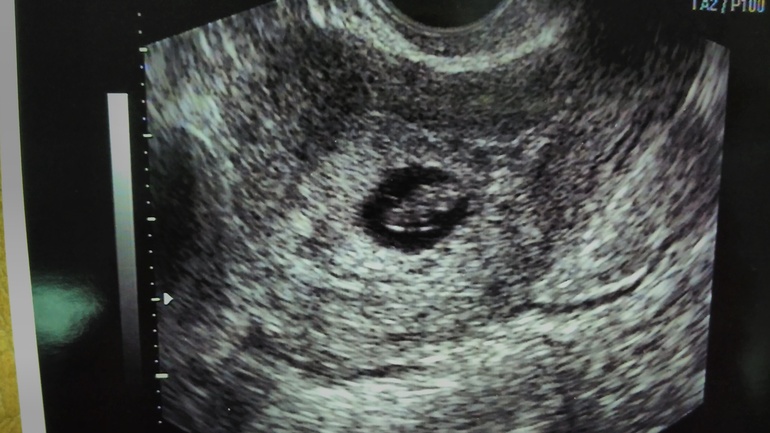

нам 8 неделек от пдм и мы счастливы!!!

9 мм были ,а увиденное сердечко просто вынос мозга